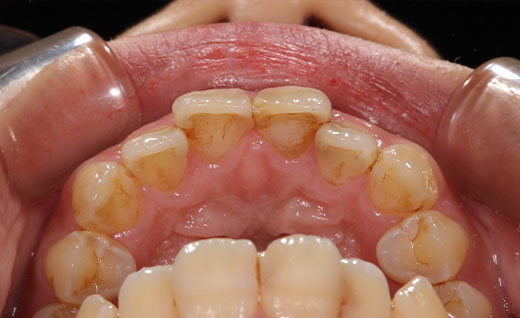

施術後

術後です。ホワイトニングをしたので術前に比べ歯は白く明るくなりました。また前歯の虫歯の治療もできるだけ目立たないように心がけ治療を行っております。術前では黒ずみや虫歯後がくっきり見えるのに対して術後ではほとんどわからず自然な見た目となります。